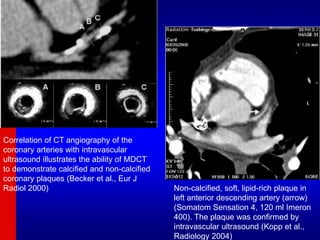

Correlation of CT angiography of the

coronary arteries with intravascular

ultrasound illustrates the ability of MDCT

to demonstrate calcified and non-calcified

coronary plaques (Becker et al., Eur J

Radiol 2000) Non-calcified, soft, lipid-rich plaque in

left anterior descending artery (arrow)

(Somatom Sensation 4, 120 ml Imeron

400). The plaque was confirmed by

intravascular ultrasound (Kopp et al.,

Radiology 2004)